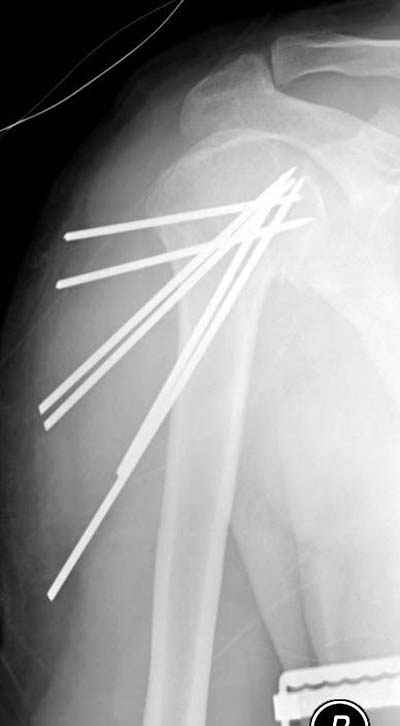

Сегодня взял больного повторно в операционную, не скажу, что повторная репозиция через неделю после первой попытки, была простая.

После удаления спиц попытался манипулировать отломками, но безуспешно, поэтому пришлось пользоваться периостальным элеватором, чтобы устранить смещение отломков и перепровести спицы. Проверил и перепроверил стабильность фиксации под ЭОПом, завтра Рг- будет готов, вот и поглядим....

Именно эти моменты+ дешевизна спиц и делают эту методику доступной практически в любых условиях (актуально для африканского государственного госпиталя). Хотя сейчас, пройдя через *подводные камни* понял , что для быстроты и простоты самой хирургии необходимо пользоваться drill sleeve and

wire guide, позволяющим ротировать пучок при его введении в головку (как объяснил Анатолий Ф.) Чтобы не терять время на поиск входного отверстия под мышцей удобно пользоваться drill sleeve 6,5 мм, удерживая его на кости после сверления отверстия, через него же провести и спицевой пучок, единственный момент который надо учитывать - чтобы размер петли не превышал диаметра протектора иначе придется начинать все сначала или в качестве альтернативы пользоваться разъёмными протекторами.